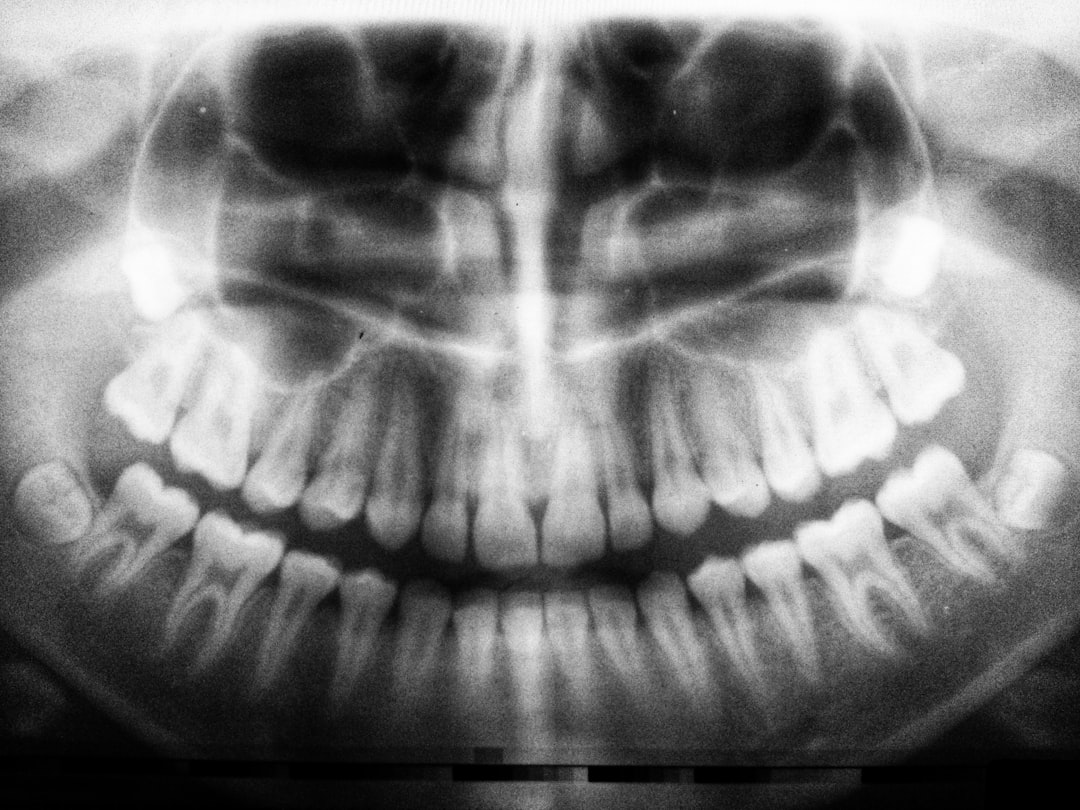

특히, 서울강남수플란트치과병원 임플란트 시술 및 후기 | 강남 수플란트치과 임플란트 가격, 후기, 예약, 수면치료는 많은 환자들에 의해 긍정적인 평가를 받고 있습니다. 이 병원의 대표적인 특장점은 체계적인 사전 상담과 환자의 편안함을 고려한 수면 치료 시스템입니다. 임플란트 시술 전에는 환자에 대한 철저한 검진과 상담을 통해 환자 개인 맞춤형 치료 계획을 수립합니다.

임플란트 시술은 단 한번으로 끝나는 것이 아닙니다. 종합적인 치료계획과 사후 관리가 필수적입니다. 의사는 주기적으로 환자의 상태를 모니터링하며 필요할 경우 후속 치료를 진행합니다. 건강한 임플란트를 유지하기 위해서는 철저한 구강 관리와 정기적인 치과 검진이 중요합니다.